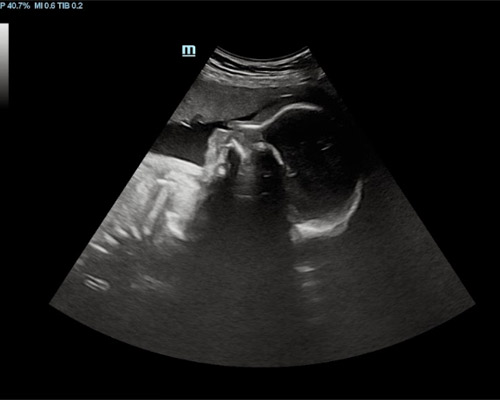

- 3D/4D ultrasound viewing (when possible)

- HD Live-style imaging for enhanced detail (where possible)

- Time to watch baby’s movements and expressions

Your comfort and safety are always a priority. Ultrasound scanning is a safe and widely used method that uses sound waves rather than radiation.

All scans are carried out using appropriate equipment and within recommended guidelines. The heartbeat recording is handled securely and prepared with care.